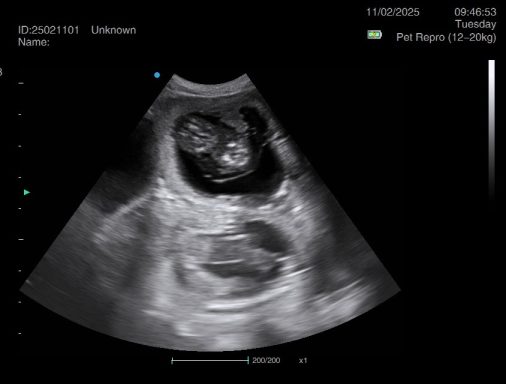

Ultrasound pregnancy scanning is a safe, non-invasive way to confirm pregnancy in dogs and cats, offering breeders and pet owners peace of mind and vital information to support responsible care. It allows us to detect gestational sacs, assess foetal development, and estimate litter size—all while ensuring the wellbeing of the animal.

Pregnancy can sometimes be detected as early as Day 18 post-mating, but scanning at this stage is not routinely recommended. Embryos are still developing and may not be clearly visible, and there is a natural risk of embryo resorption, which can lead to misleading or inconclusive results.

For the most accurate and reliable scan, we advise booking between Day 25 and Day 32, when pregnancy is more easily confirmed and foetal structures are clearer. If an early scan is performed and no pregnancy is detected, we offer a FREE complimentary re-scan after 7 days at the clinic to ensure clarity and support informed decision-making.

Our approach balances early insight with ethical care—always prioritizing the comfort of the animal and the accuracy of the results.